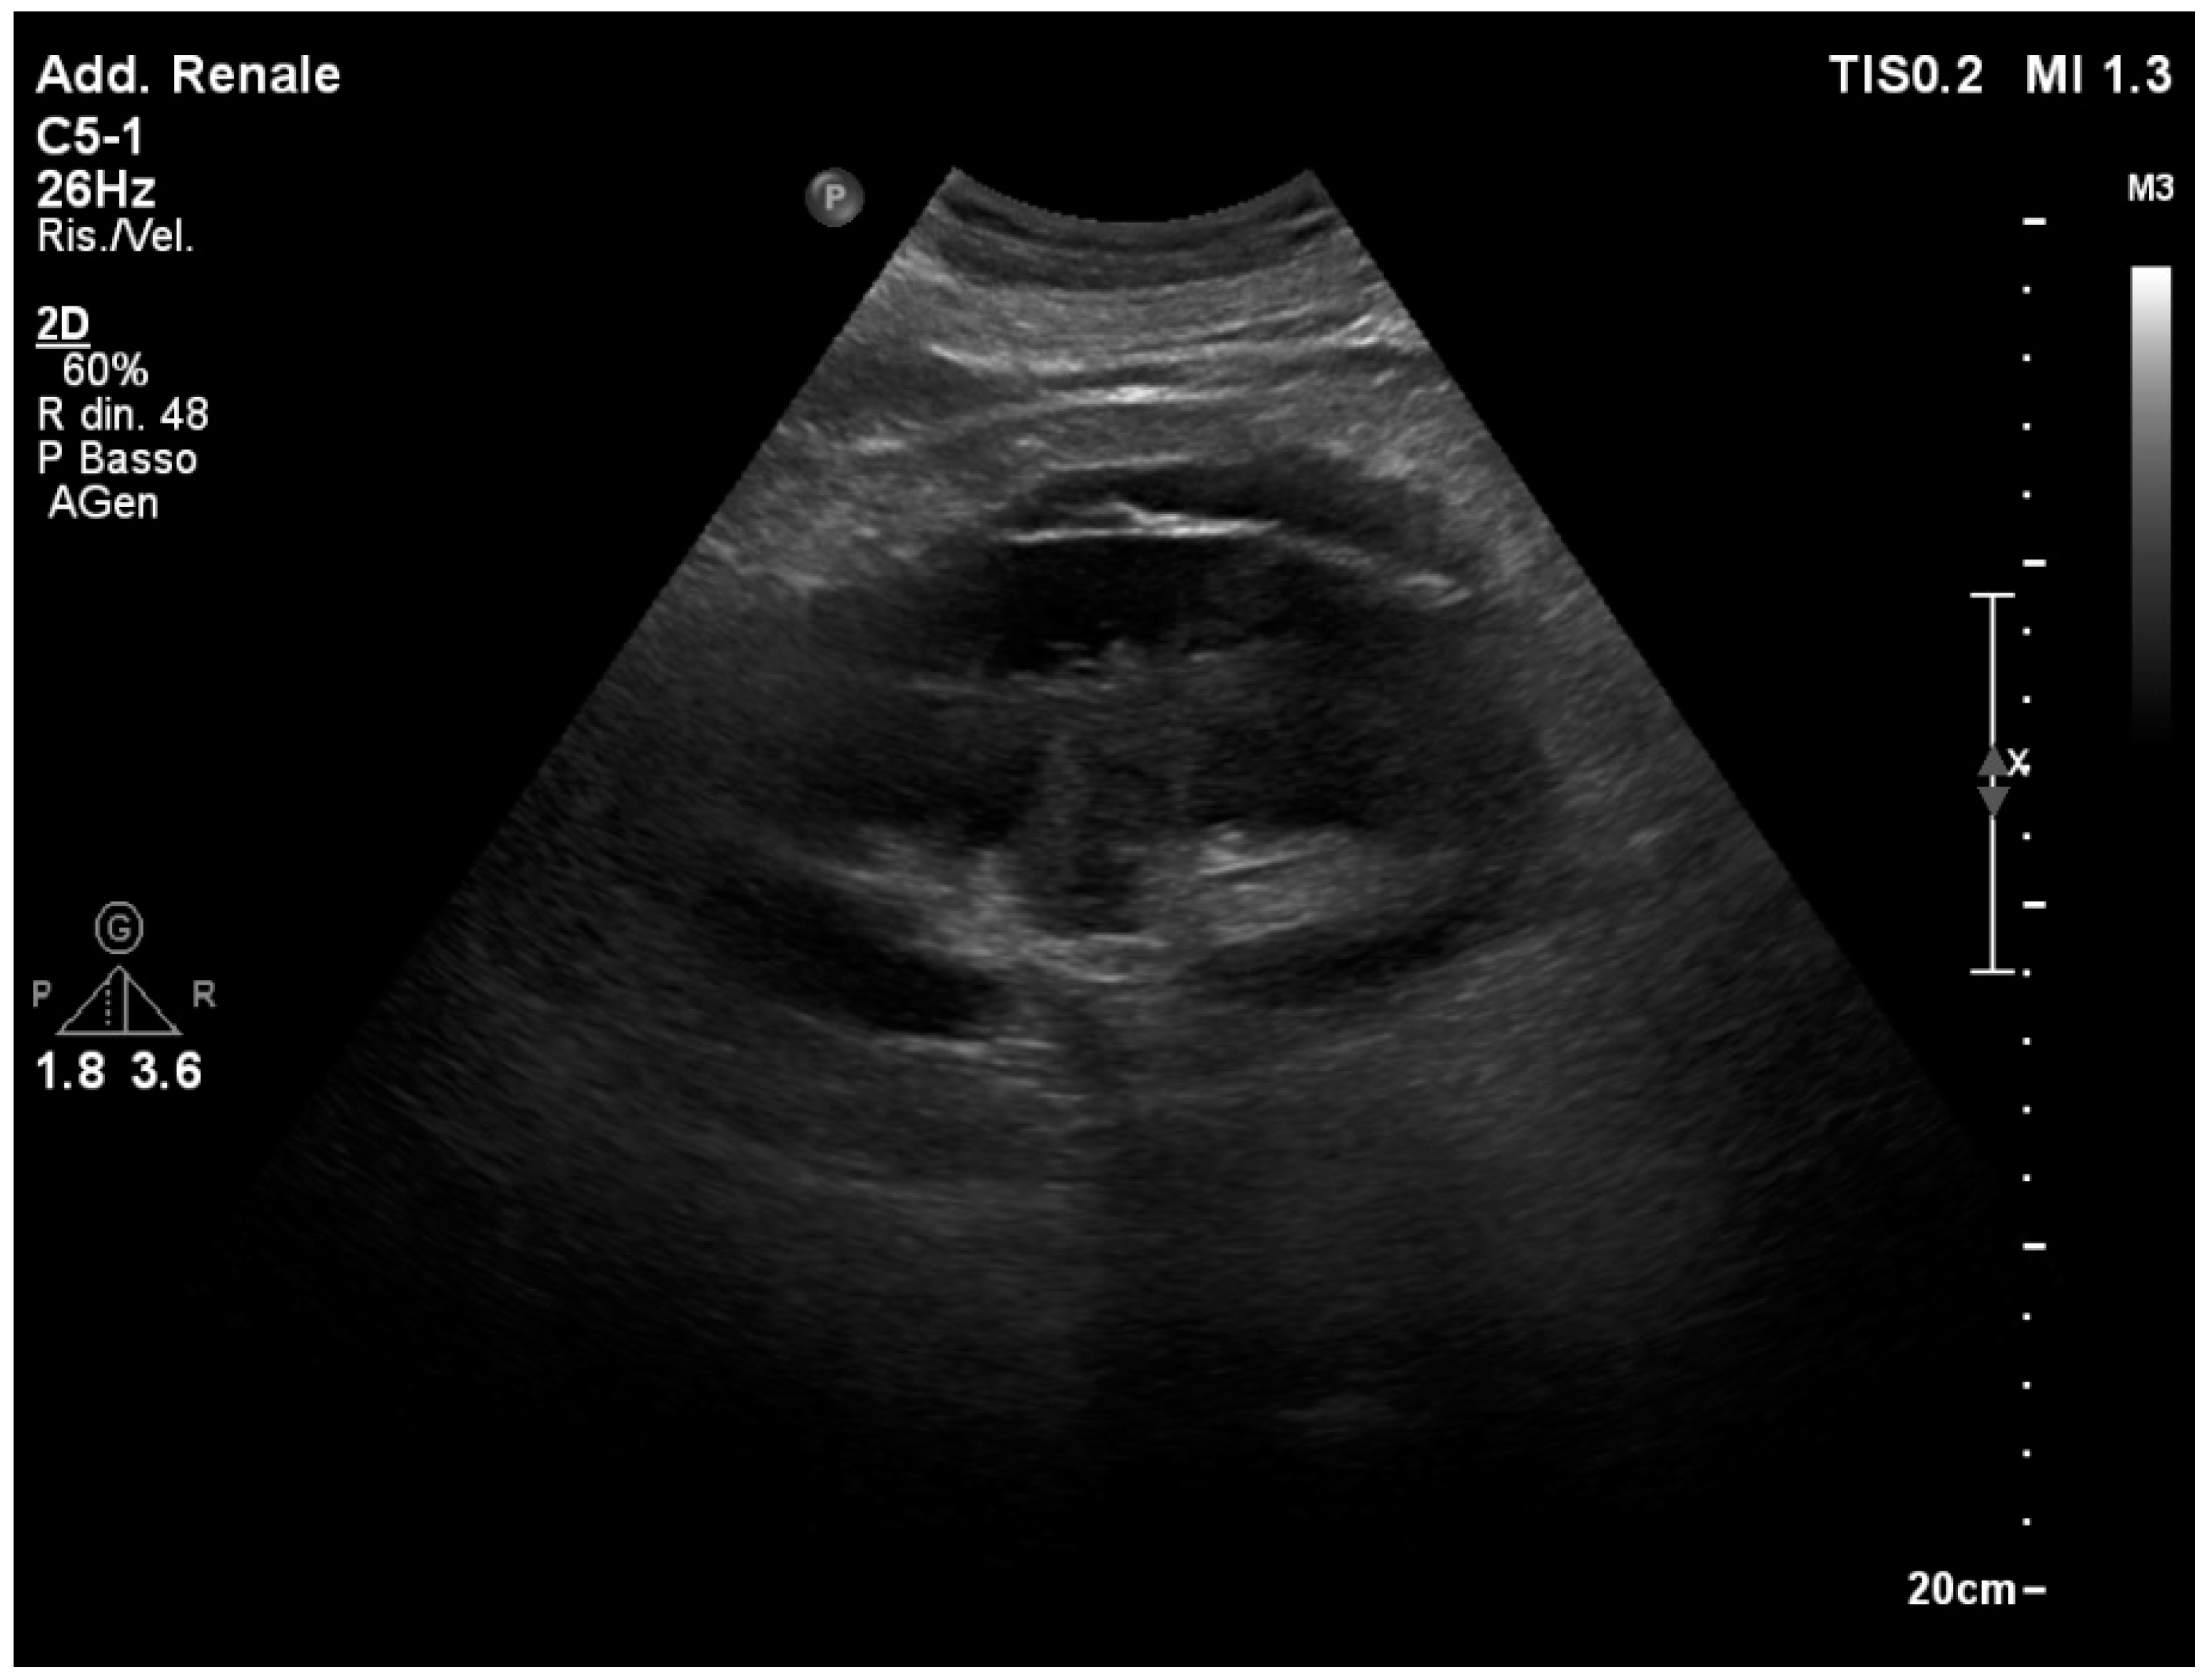

3.1. Normal Sonographic Anatomy